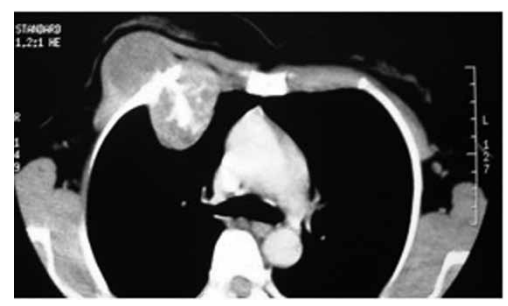

Paciente 45 anos, com abaulamento em região torácica

anterior há 2 anos. Exame físico: lesão endurecida, pouco móvel, pouco dolorosa, em região anterior de hemitórax direito.

Tomografia de tórax a seguir:

Biópsia demonstra: hipercelularidade, condrócitos com núcleos volumosos e as vezes binucleados, polimorfismo, atipias, matriz celular mixoide, invasão e destruição de trabéculas ósseas adjacentes.

O diagnóstico do paciente é de